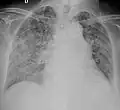

A case of miliary tuberculosis in an 82-year-old woman:

X-ray, 13 days after onset, showing bilateral interstitial infiltrates -

X-ray, 22 days after onset, showing extensive bilateral reticulo-nodular infiltrates -